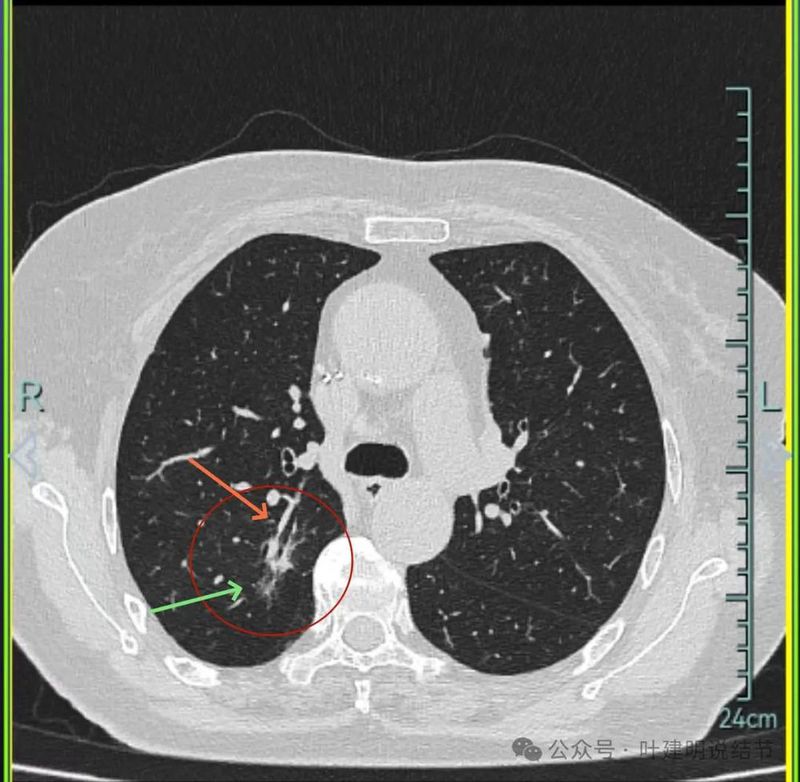

主病灶连续层面展示分析:

病灶出现,磨玻璃密度,轮廓与边界均清楚,灶内密度稍不均。

有明显血管进入,表面分叶,边缘不平,整体轮廓清。

边缘毛刺、表面不平、灶内偏实性成分、分叶明显,整体轮廓与瘤肺边界较为清楚。

灶内细支气管扩张、边缘毛刺较为锐利、有明显磨玻璃成分,磨玻璃成分的瘤肺边界清楚,病灶分叶明显。

灶内密度杂乱不均,内有小空泡征,表面不平。

灶内血管增粗穿行、磨玻璃成分明显,轮廓较清。

血管进入,磨玻璃成分,支气管扩张,边缘不平。

典型混合密度病灶,中间部分密度高偏实性,外围部分磨玻璃密度,两者之间交错存在,说明偏实性部分有侵袭性。磨玻璃成分与正常肺组织之间界限清楚,表面分叶,部分边缘毛刺,整体轮廓清。是非常符合恶性的影像表现。

灶内磨玻璃成分明显,并有异常增粗血管僵硬穿行于病灶内,支气管有扩张通气征,瘤肺边界清楚,实性成分明显。